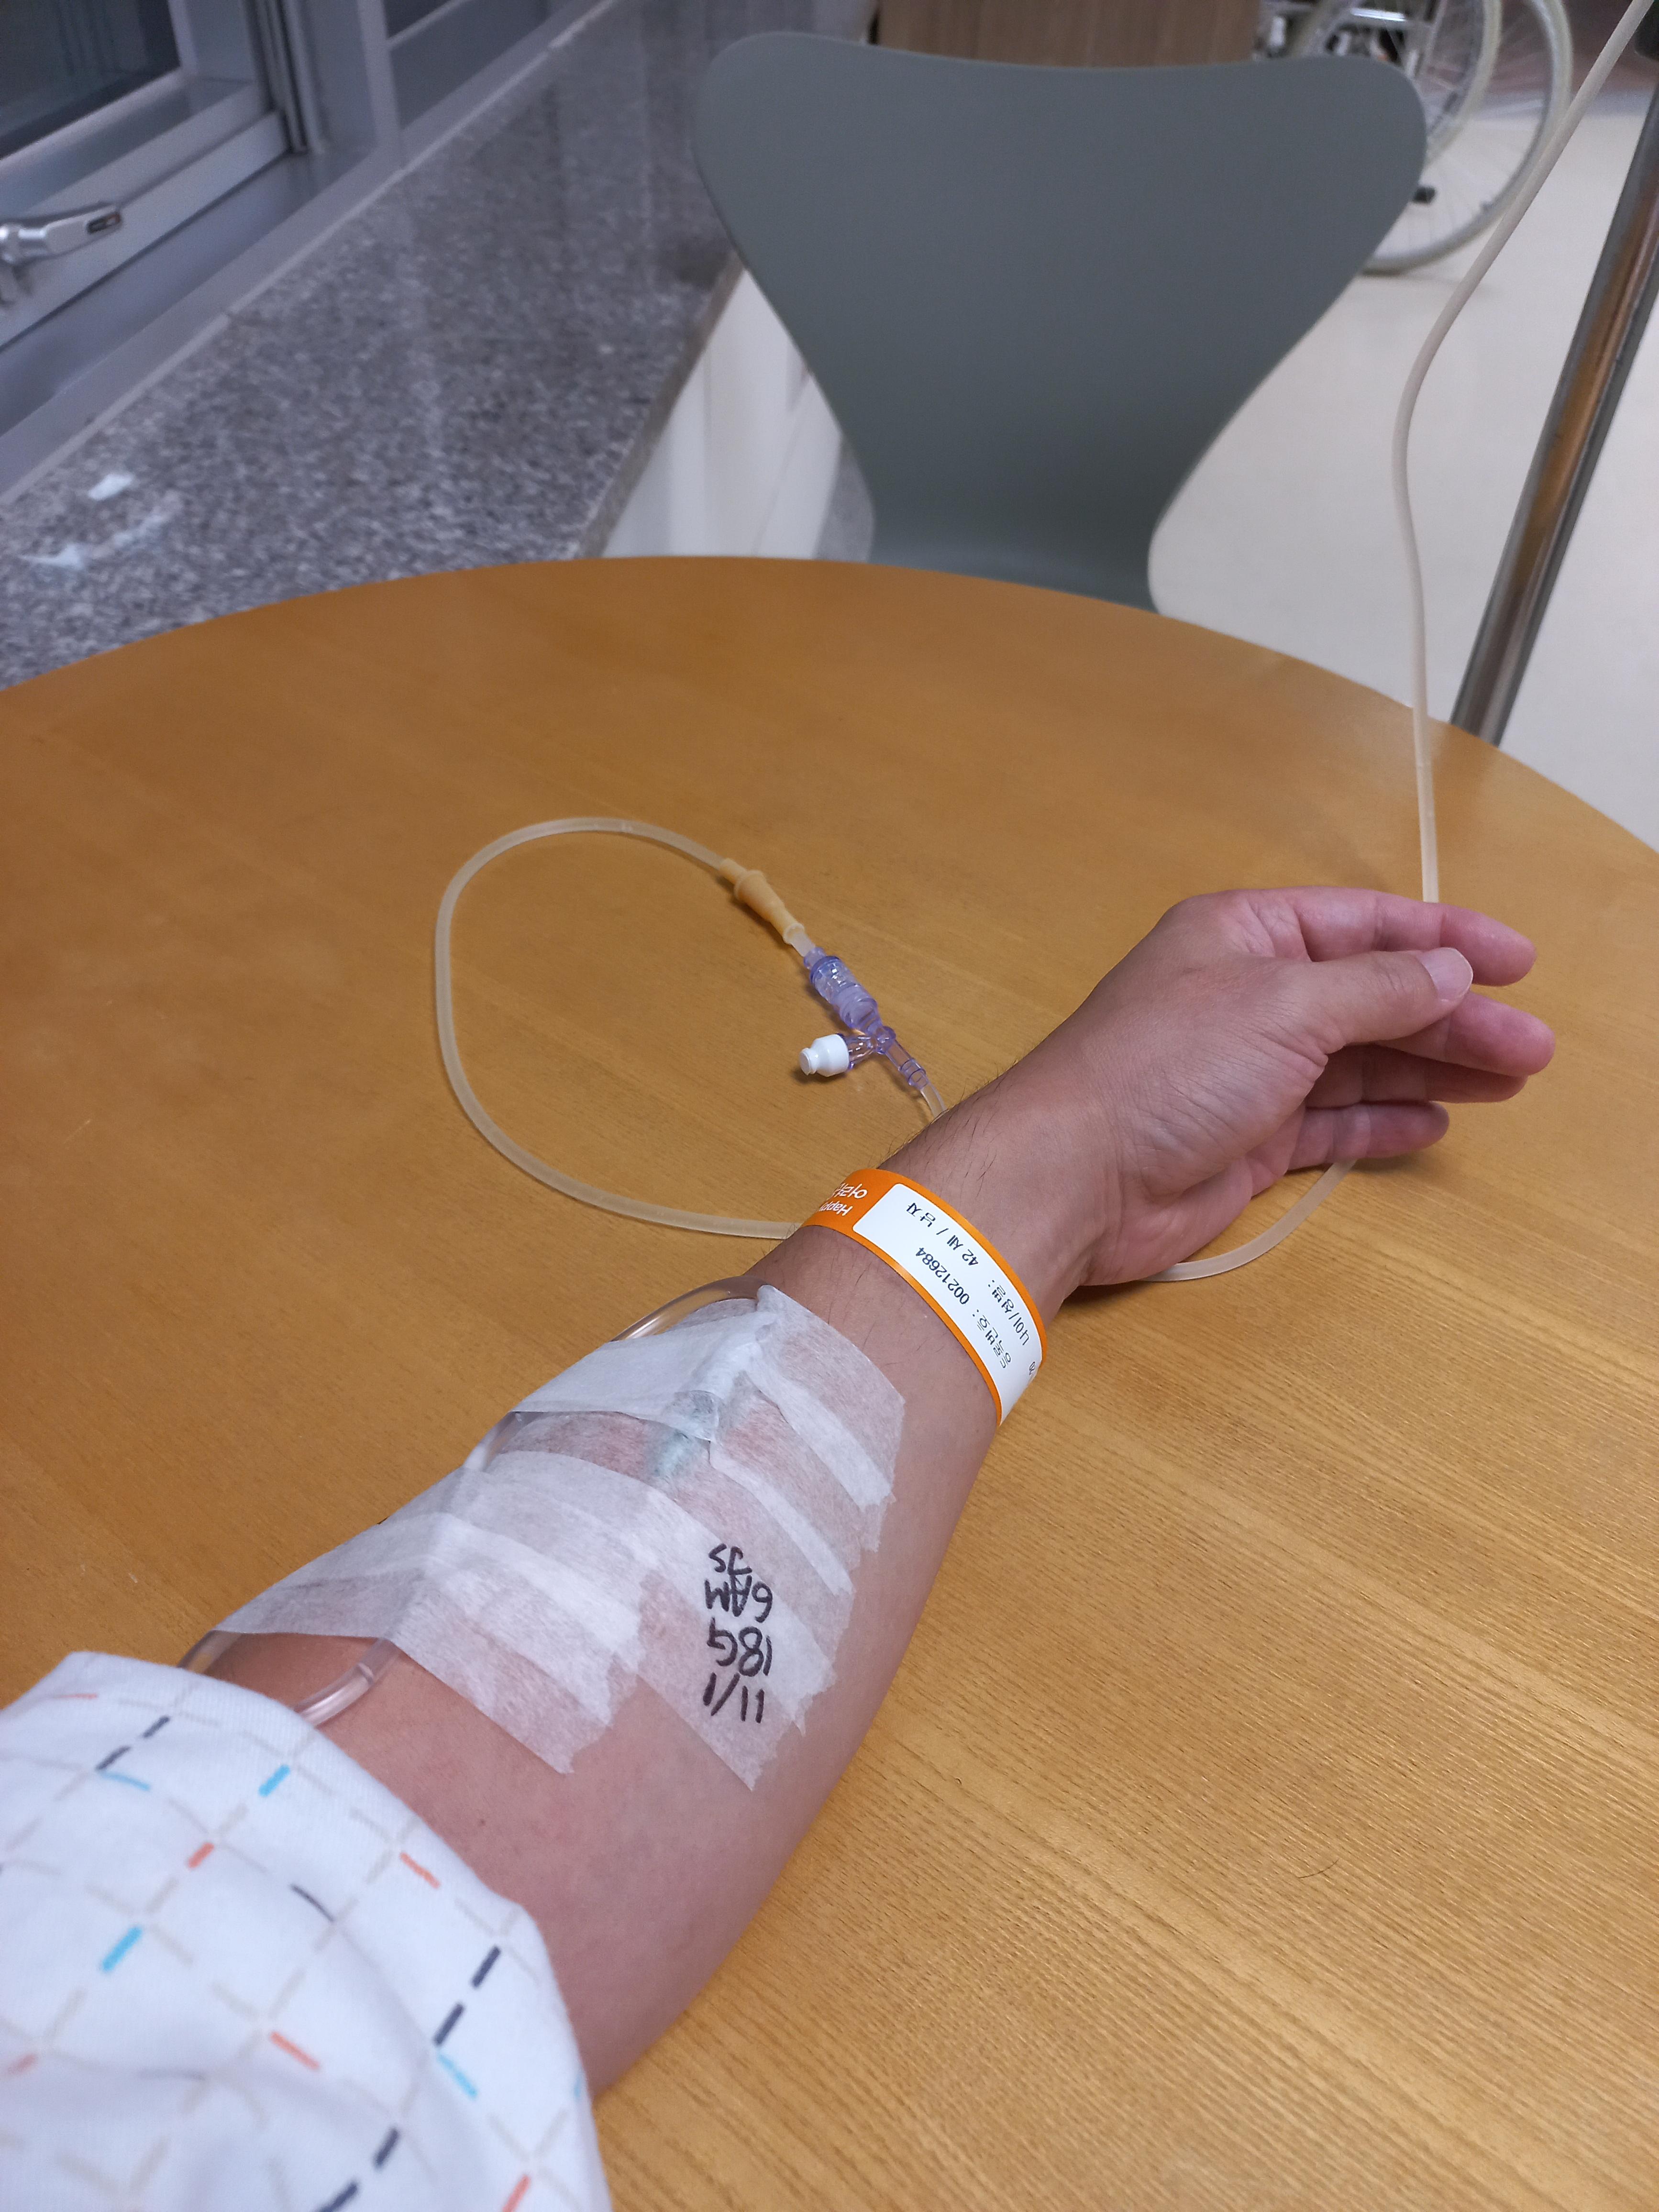

입원 후 주사 꽂는걸 워낙에 싫어해서 대바늘 주사를 안 꽂으려고 했는데

수술할때 필요하다고 안아파도 대바늘 꽂고 닝겔 맞아야 하더군요..

병원갈때 마다 느끼는 거지만 정말 주사 맞기 싫습니다. ㅠㅠ

수술은 오전에 했는데 저녁때에 정신차리고 사진 찍었네요